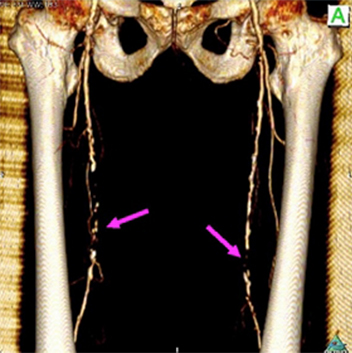

<手術前>両側総腸骨動脈(お腹の中にある足のつけねの動脈)と両側大腿動脈(太ももの動脈)に閉塞、狭窄部位があり、運動障害(間歇性跛行)や皮膚障害(壊死)を引き起こし、車椅子に乗られての入院となりました。

<手術後>右の鎖骨下~腋窩動脈(鎖骨の下から脇の下にかけての動脈)から両側大腿動脈、さらにそこから両側膝窩動脈(膝の裏の動脈)にバイパス手術を施行しました。

運動障害、皮膚障害も改善し、歩いて退院されました。

両側総腸骨動脈狭窄、閉塞

両側大腿動脈狭窄、閉塞